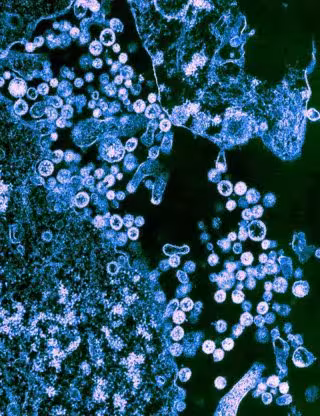

Archivo - Las partículas de la cepa Josiah del virus Lassa (redondo) se muestran en gemación de las células.

Archivo - Las partículas de la cepa Josiah del virus Lassa (redondo) se muestran en gemación de las células. - UNIVERSIDAD DE TEXAS - Archivo